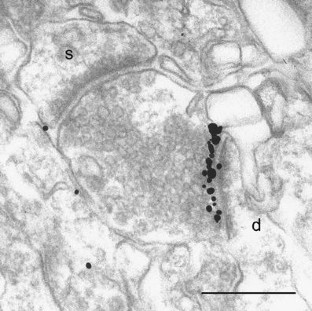

Nusser Z, Mulvihill E, Streit P, Somogyi P (1994) Subsynaptic segregation of metabotropic and ionotropic glutamate receptors as revealed by immunogold localization. Neuroscience 61:421–427

Lujan R, Nusser Z, Roberts JD, Shigemoto R, Somogyi P (1996) Perisynaptic location of metabotropic glutamate receptors mGluR1 and mGluR5 on dendrites and dendritic spines in the rat hippocampus. Eur J Neurosci 8:1488–1500

Lujan R, Roberts JD, Shigemoto R, Ohishi H, Somogyi P (1997) Differential plasma membrane distribution of metabotropic glutamate receptors mGluR1 alpha, mGluR2 and mGluR5, relative to neurotransmitter release sites. J Chem Neuroanat 13:219–241